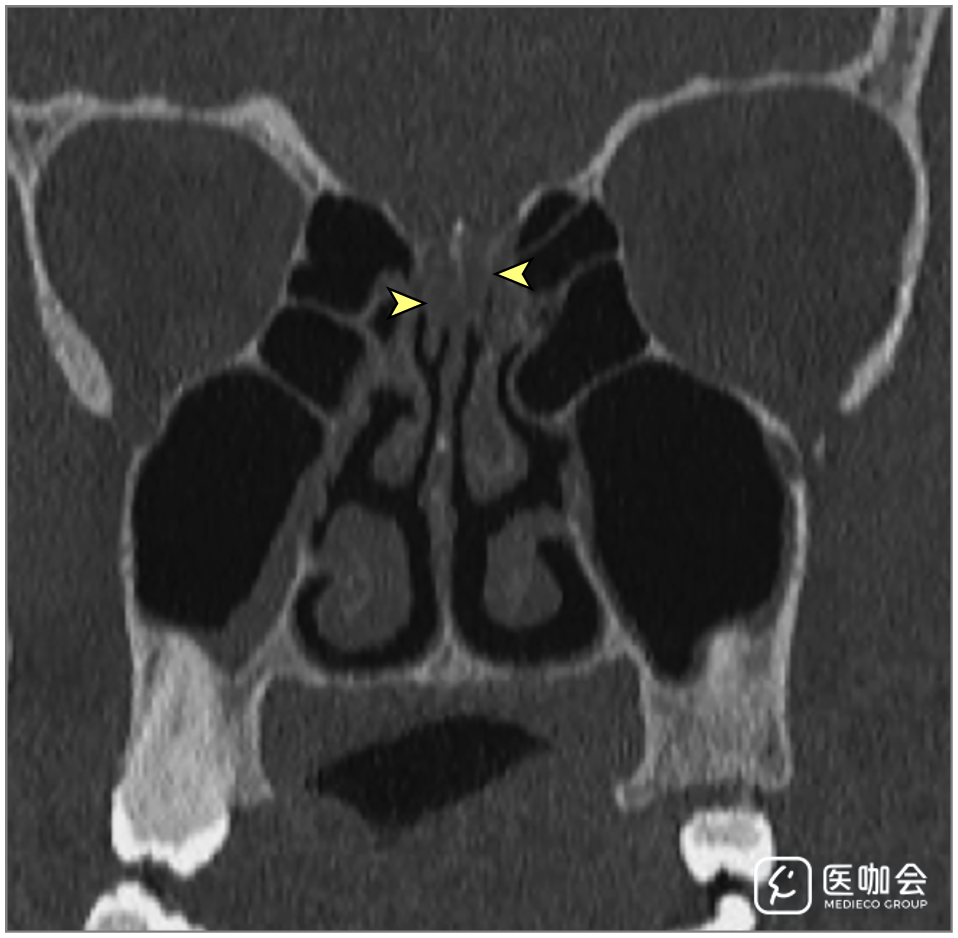

患者接受了鼻腔CT检查(图1),显示双侧嗅裂区的炎性阻塞,经鼻腔MRI再次确认了这一结果(图2)。患者的嗅球和嗅神经束未见异常。由于她的丈夫被怀疑感染了SARS-CoV-2,因此该患者也接受了SARS-CoV-2的RT-PCR,结果呈阳性。

图2